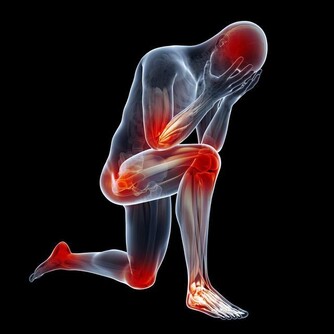

但當病情嚴重時會引起非常糟糕的狀況,

例如腿麻、皮膚蒼白、心絞痛、心率過快、心力衰竭等。